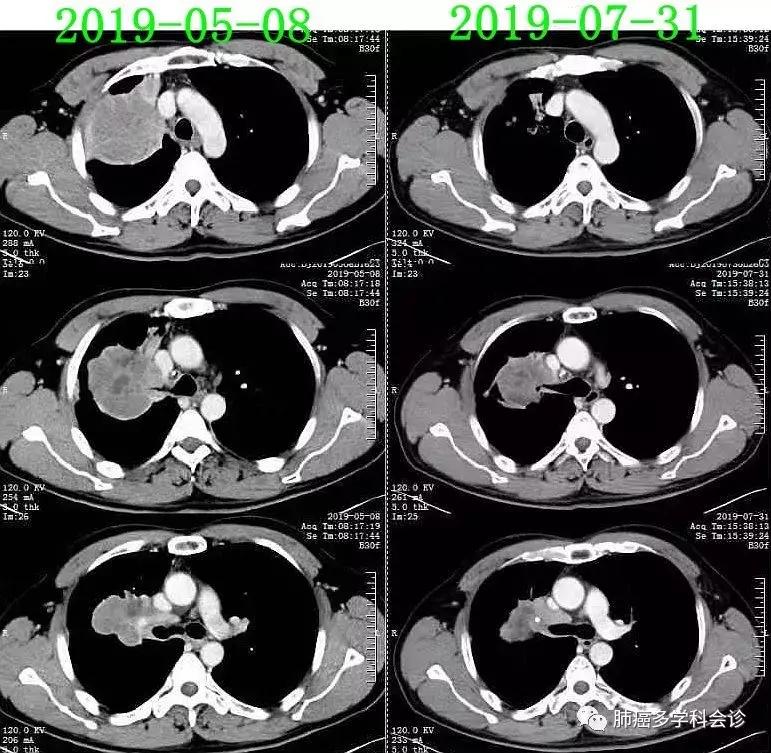

于2019.6.29(距第1周期51天)进行第二周期“PD-1单抗+安罗替尼”治疗。

2019.7.31(治疗2个周期后32天)复查CT,肿瘤明显退缩,疗效评价:PR。

于2019-08-01(距第2周期33天)进行第三周期“PD-1单抗+安罗替尼”治疗(因患者推迟返院日期)。